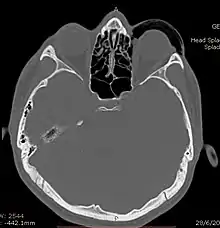

Woman with preorbital swelling in orbital emphysema shown in CT scans | |

Computed tomography (CT)

Computed tomography is effective and sensitive in the diagnosis of orbital emphysema,[3][37] as it can confirm the anatomical location and size of air, bony defects, indentation of the eyeball, and the condition of the optic nerve, as well as the presence of any extraocular muscle entrapment and herniation of preorbital fat into the sinus cavities.[3][15][38] The location of the orbital emphysema is present near the site of the fracture.[1][3] The scans are usually taken along the transverse plane. Transverse images allow the evaluation of fractures in medial and lateral orbital walls. By reformatting these transverse images or taking coronal images, the examination of orbital floor and roof is permitted. Helical scanning is preferred as it has a lower imaging time and radiation dose comparing to conventional scanning, especially when reforming transverse helical scans into coronal images.[3] The staging of orbital emphysema can then be determined with visual acuity examination and ophthalmoscopy.[6] A disadvantage of using a CT scan is that when detecting air after orbital trauma, the presence of a wooden foreign object can give a false positive result of orbital emphysema. The wooden object can mimic the presence of orbital emphysema. Therefore, patients’ medical history is crucial in making the correct diagnosis.[3]